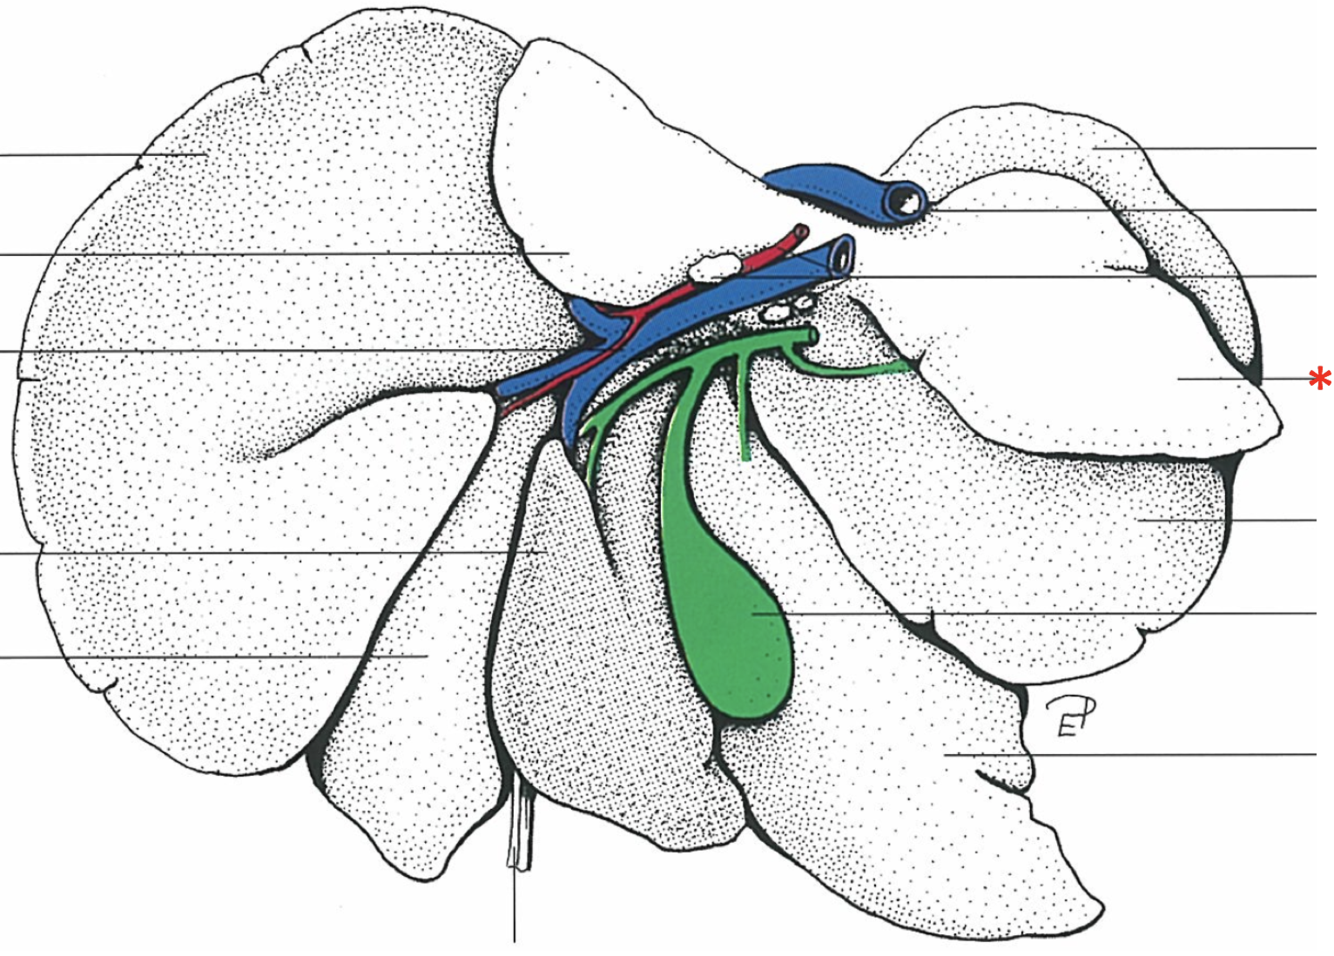

The Caudate Process extends from the…

Lobus caudatus

The sharp-edged border of the liver is called…

Margo acutus

The blunt-edged border of the liver is called…

Margo obtusus

Ligg.falciformehepatiset tereshepatis

18

Lig. coronale hepatis

15